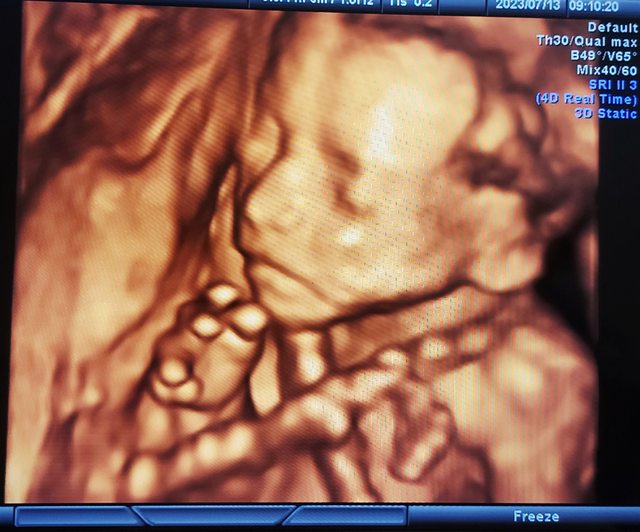

: 附上一張寶寶高層次的帥照,

: 希望他可以平安的來到媽媽身邊陪伴我們

: https://i.imgur.com/Ns2W6U1.jpg